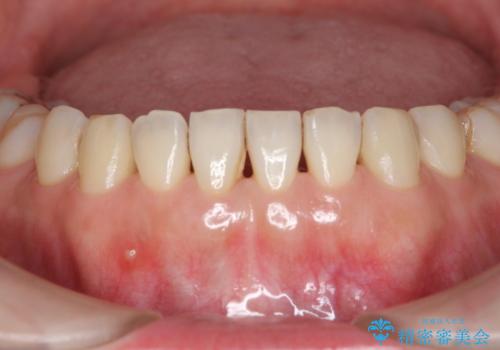

最近右下の犬歯の根の先付近の歯茎に何かできており、違和感があるとのでした。

CTでみたところ、下の犬歯が内側に倒れこんでおり、根の先が顎の骨から出かかっている状態でした。おそらくその影響で犬歯の神経が失活してしまったのであろうと思われます。(フェネストレーションといいます)

検査した結果下の両側の犬歯の神経が失活しており、根の治療が必要な状態でした。